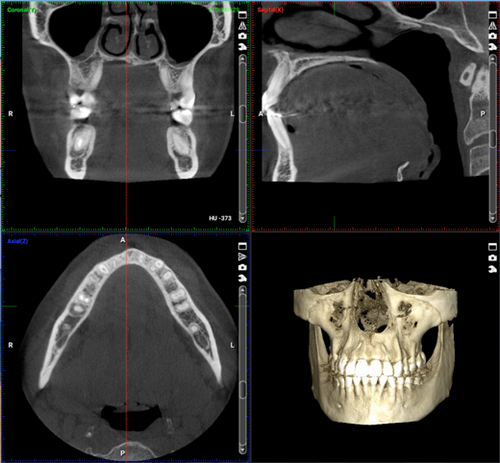

Con el 3D radiológico conseguimos imágenes volumétricas del hueso de la cara del paciente. Así vemos la posición real de las articulaciones, esto es importantísimo para comprobar que tienen una buena función. También hay que destacar que esta imagen, del volumen de los huesos, es clave para que el cirujano pueda ver los cambios que va a haber en la cara del paciente de forma muy real, así pues, podemos decir que permite hacer una cirugía virtual. Nos bastan 16 segundos para hacer esta radiografía volumétrica o CBCT (Cone Beam Computed Tomography). Es una prueba similar a un TAC, pero en este caso sólo hace falta una rotación de emisión de Rayos X y en el TAC se necesitan varias rotaciones, así la radiación que recibe el paciente es muy baja (75 CBCT equivalen a 1 TAC convencional). La imagen que obtenemos para poder diagnosticar puede ser desde la imagen de un solo diente hasta el cráneo completo, dependiendo del paciente y del caso a tratar.

Por otra parte, con las pruebas 3D nos evitamos hacer 3 radiografías al paciente. Hasta ahora necesitábamos realizar una ortopanto, una teleradiografía lateral y una frontal. No obstante, no conseguíamos toda la información que queríamos (faltaba la posición de las articulaciones). Con un simple CBCT la radiación es menor que las 3 radios y recibimos muchísimos más datos. Además, con el escaneado de la boca nos evitamos tomar medidas con alginato que en los casos quirúrgicos lo hacemos cada 3 meses.

Otro avance importante, para el paciente y su tratamiento, es la precisión. En los casos de ortodoncia que requieren de colocación de microtornillos en el paladar, para ayudar en el tratamiento, podemos situarlos sabiendo donde está exactamente el nervio y la raíz del diente. También cual es lugar ideal para posicionar el tornillo y cómo debe de ser su grosor y tamaño, teniendo en cuenta el espacio que tiene el paciente en su boca. Ya no hay que ir probando ya que ahora todo es precisión y exactitud.